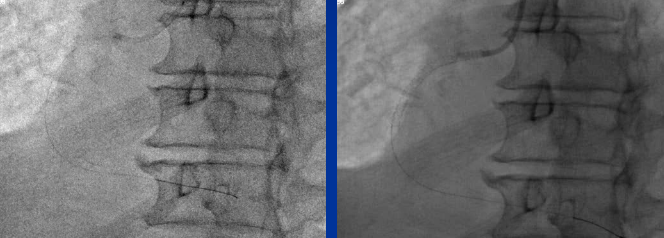

【影像学检查】

CAG (2016-1-4)

RCA-PCI

LCX-PCI (2016-1-7)

RE-CAG: (2016-2-10)

入路:右桡 6F JR4.0 右股7F EBU3.75

Fielder XT Finecross LEGEND 1.25*15mm

VOYAGER 2.5*15mm、Excel 2.5*36mm、Excel 2.75*36mm